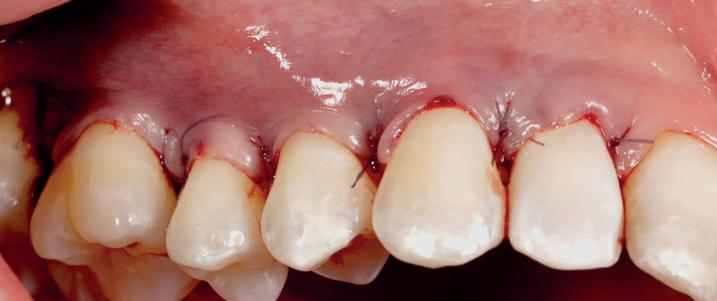

EthOss® is a 100% synthetic bone graft material for dental implant surgery. With no risk of cross-contamination, EthOss® works with the body’s healing process by creating a calciumrich environment and is completely absorbed.